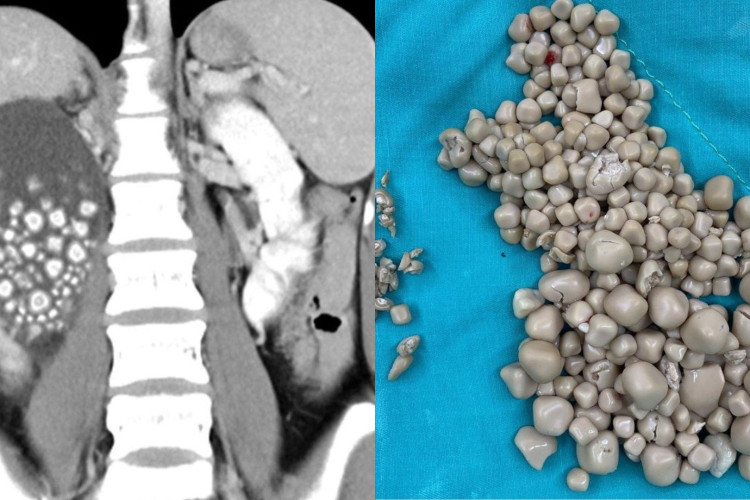

A mulher foi submetida a uma radiografia que revelou inchaço em seu rim direito além da presença de centenas de pedras alojadas no órgão. Os médicos prescreveram antibióticos e realizaram uma pequena intervenção para remover as pedras. Mais de 300 pedras foram retiradas com medidas entre 0,5 até 2 centímetros de diâmetro.

O cirurgião-chefe Lin Caiyang classificou as pedras como semelhantes a pequenos pães cozidos no vapor. Quando questionada sobre hábitos alimentares, que poderiam acarretar formação de cálculos renais, a jovem alegou não beber água há anos, substituindo o líquido por chás, sucos e bebidas alcoólicas.